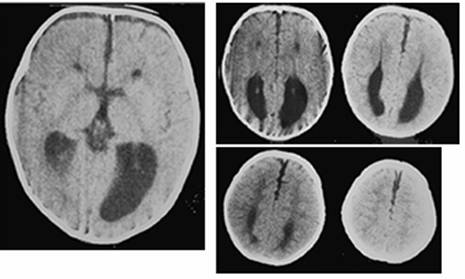

Figure 3

Clinical and image aspects of patient 3